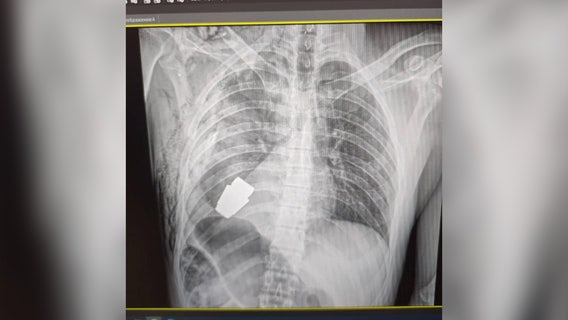

Ukrainian surgeons successfully remove live grenade from soldier's body

The unidentified soldier is recovering and will receive further rehabilitation.